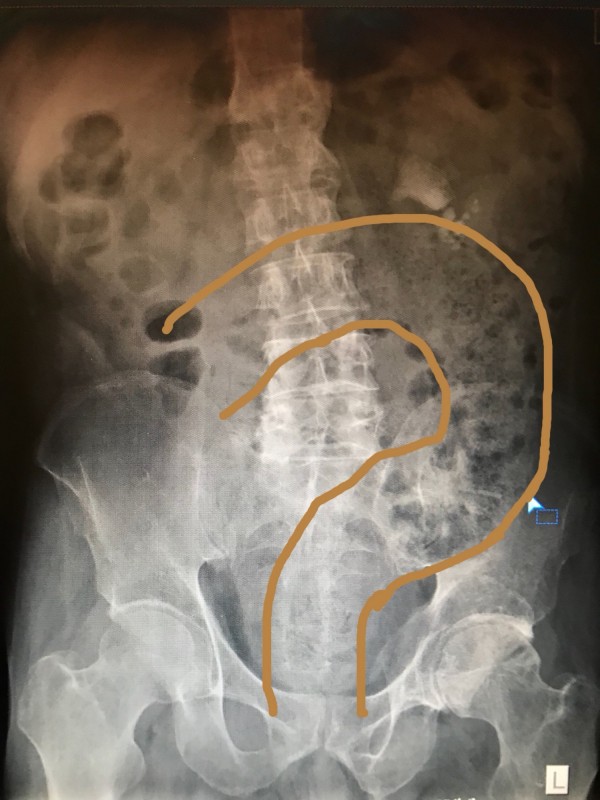

送到醫院時,不斷哀號腹痛不止,表明自己超過4天沒有解便,緊急照X光片了解後,發現

男子整個腸道腫脹塞滿了糞便堆積,只能採取徒手挖的方式輔助排出,最後累積排出約4

男子肚子內堆滿排不出去的糞便。黃線為糞便。